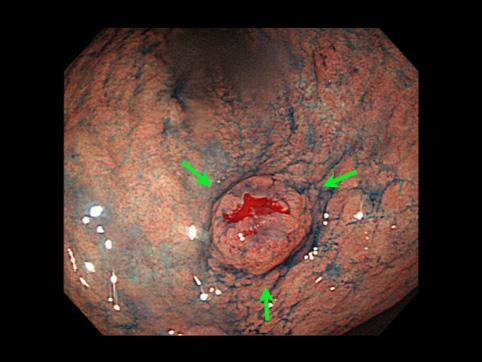

“사마귀”모양의 융기가 다발한 위의 과형성 용종

[Image-ID:10883]

종양양 병변/과형성 용종

위(부위)/2개 이상

종양의 최대경(밀리미터)

10~14